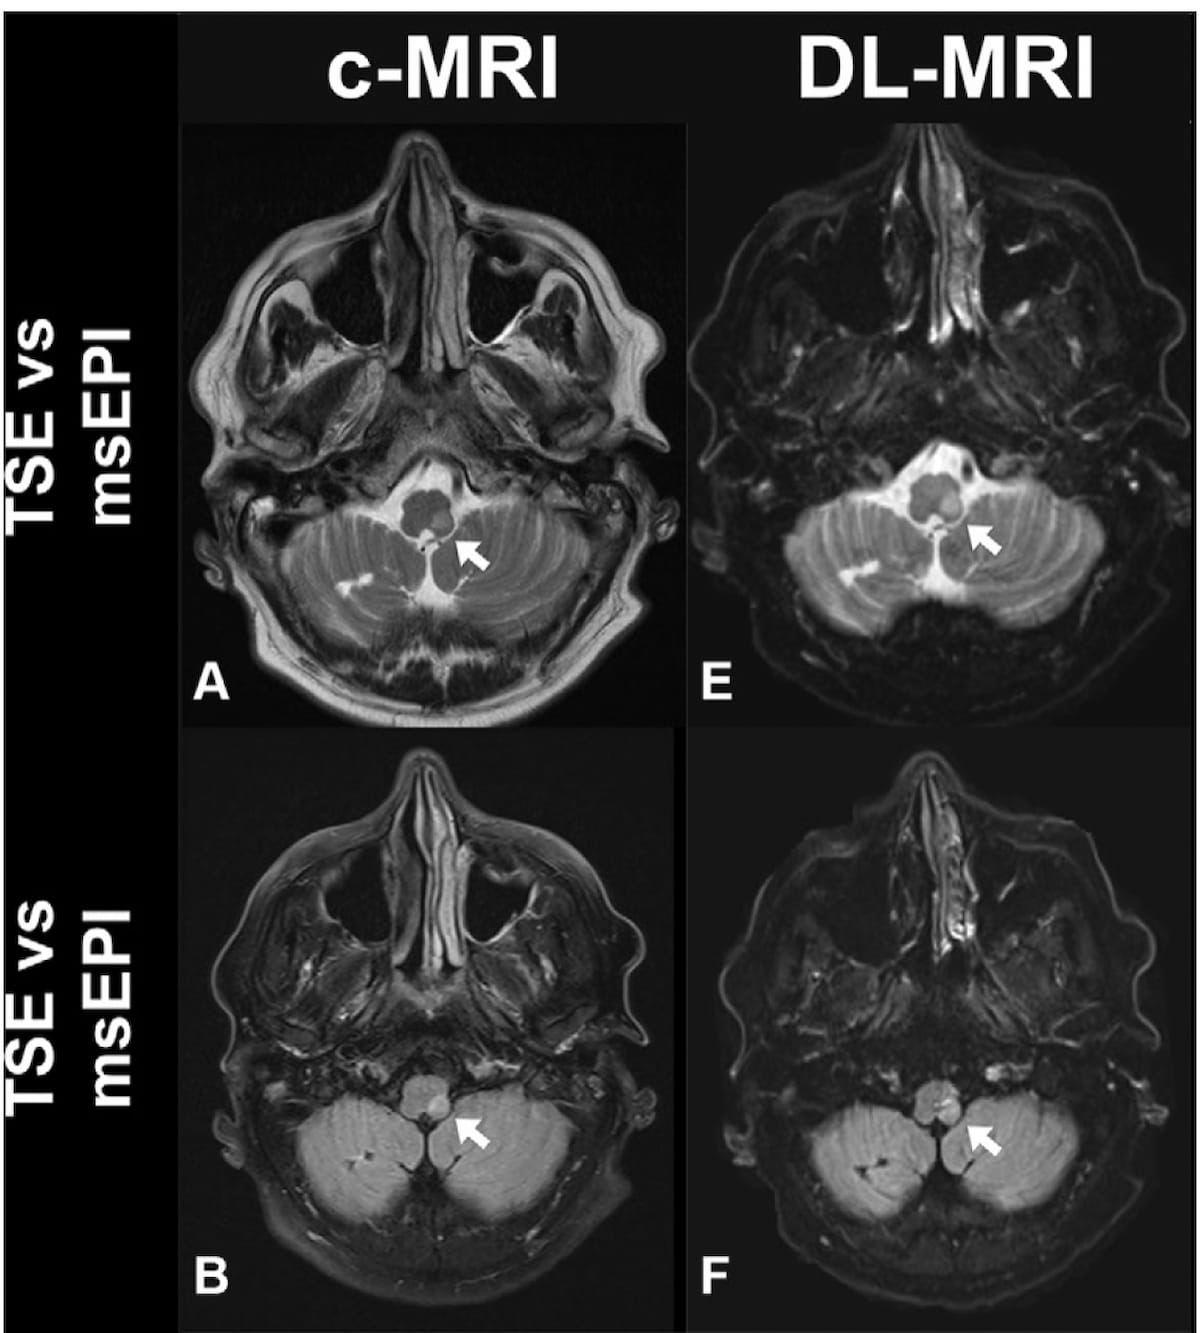

Here one can see a comparison of conventional MRI and deep learning accelerated MRI that reveal acute infarction in a 75-year-old man. Researchers noted excellent image quality with deep learning accelerated MRI in 77.1 percent of readings in comparison to 61.9 percent of readings with conventional MRI. (Images courtesy of Radiology.)

Three reviewing radiologists also noted higher image quality with DL accelerated MRI. Out of 633 readings with DL accelerated MRI, the reviewing radiologists noted excellent image quality for 488 readings (77.1 percent) in comparison to 61.9 percent (392 of 633 readings) for conventional MRI.

The researchers also noted significant reductions in scanning time for DL accelerated MRI. The T2-weighted transverse plane sequence had an average acquisition time of 2 minutes, 39 seconds with conventional MRI vs. 24 seconds with DL accelerated MRI. T2 FLAIR sequences were completed in three minutes, 20 seconds on average with conventional MRI in comparison to one minute 22 seconds with DL accelerated MRI. Overall, the study authors noted a significant reduction in image acquisition time with DL accelerated MRI (14 minutes 18 seconds) in contrast to conventional MRI (3 minutes 4 seconds) for the detection of acute ischemic infarction.